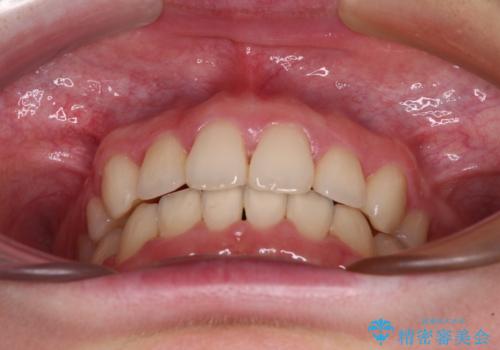

- 上顎前歯のデコボコを気にして来院された患者様です。

口元の突出感はなく、上顎のみに顕著な叢生が認められました。

上顎の左右第一小臼歯2本を抜歯し、ワイヤー装置にて歯列を整えることとしました。